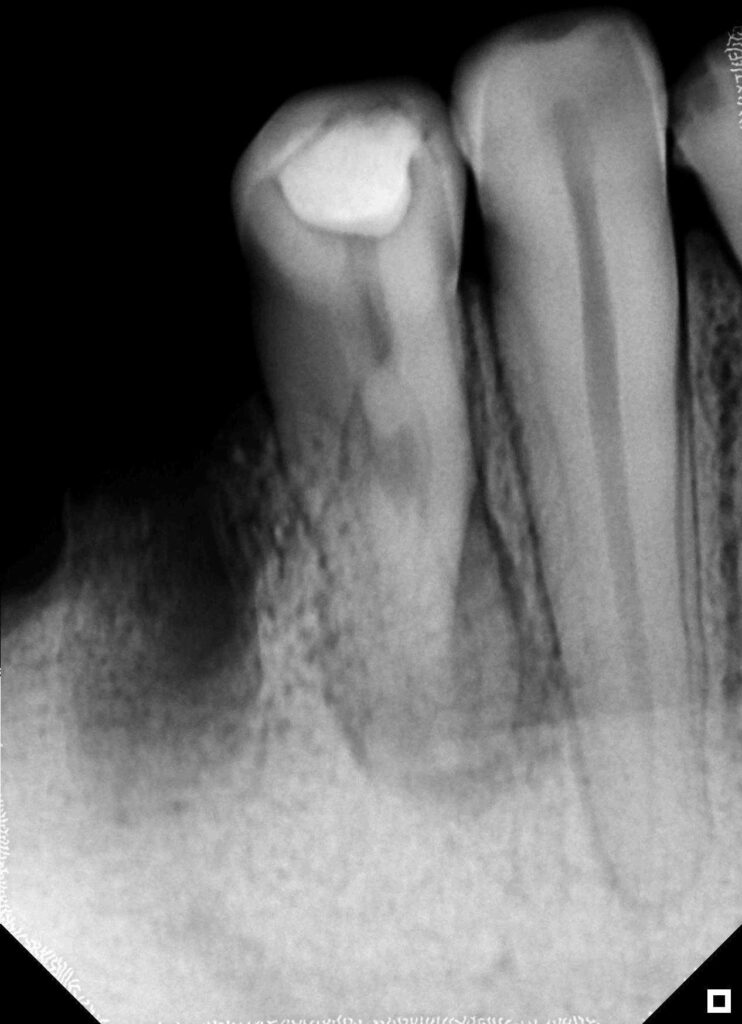

Evaluación radiográfica preoperatoria

La radiografía inicial revela una imagen sugerente de una división abrupta del conducto

principal antes del tercio medio. Se observa ensanchamiento del espacio del ligamento

periodontal e imagen radiolúcida apical, una anatomía radicular compleja que sugiere la

presencia de múltiples sistemas de conductos.